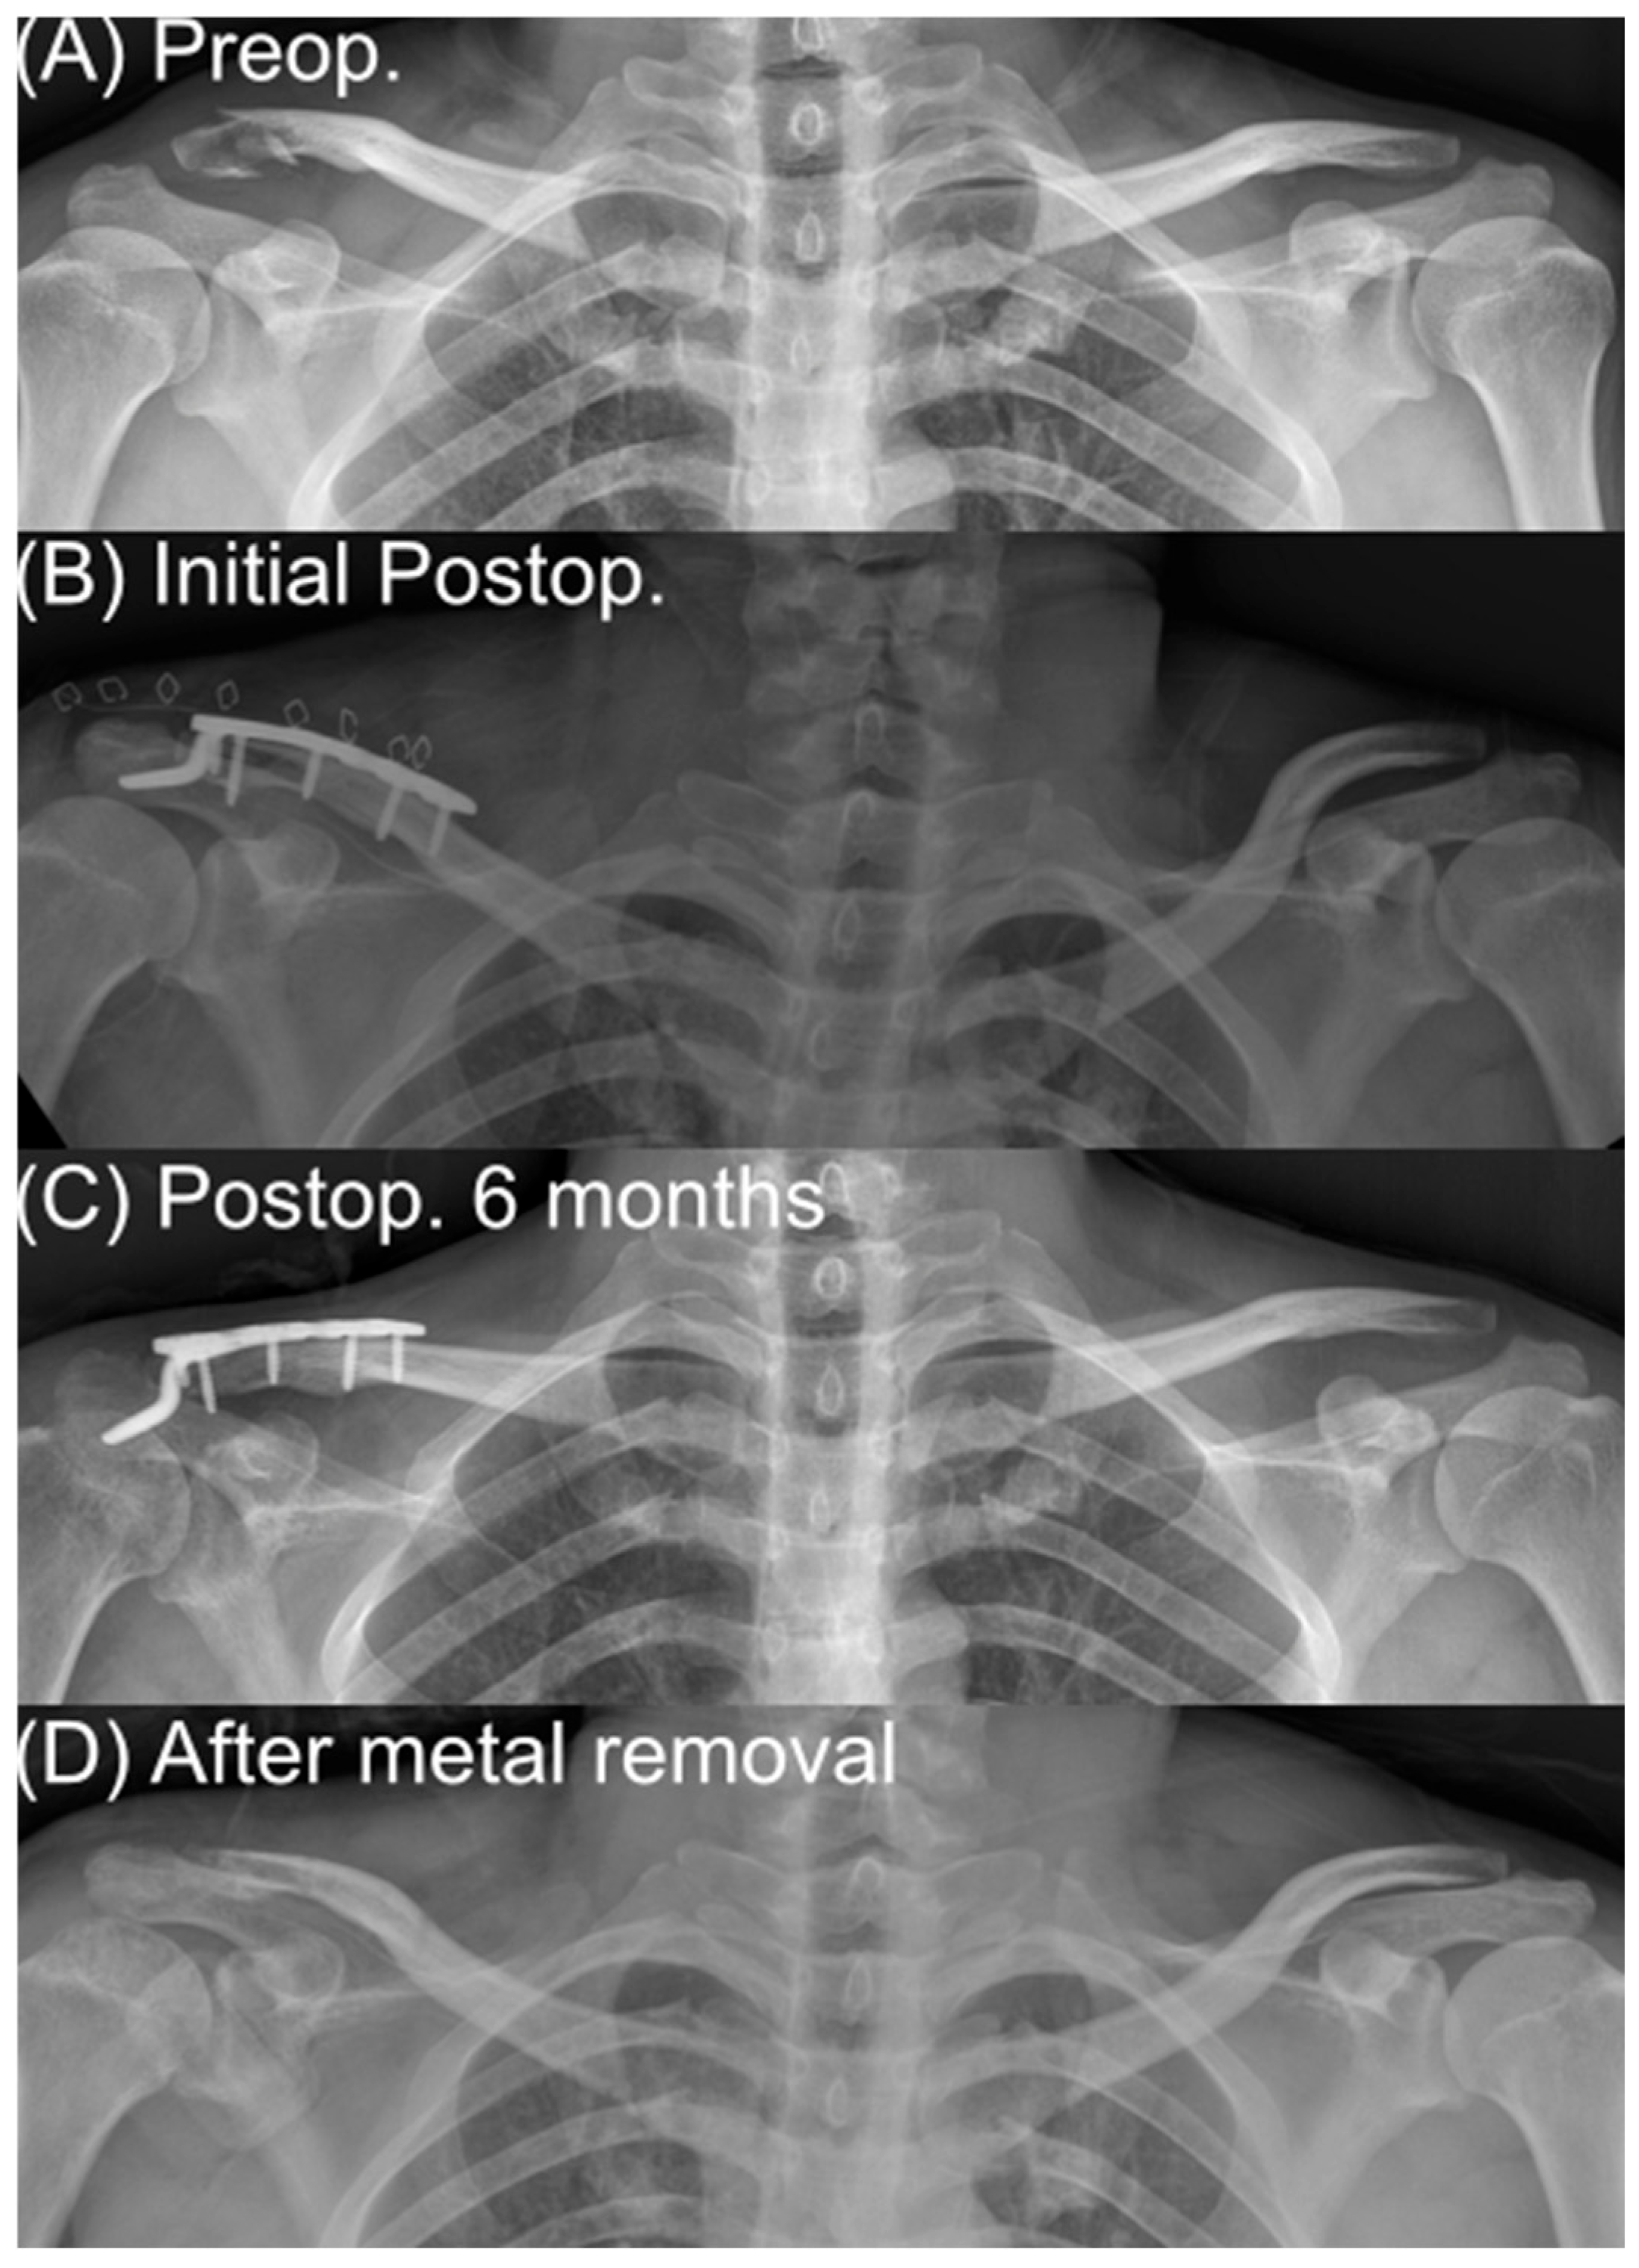

A 35-year-old man who sustained a distal clavicle fracture in a traffic accident was treated with hook plate fixation. (A) is a preoperative anteroposterior radiograph demonstrating an unstable distal clavicle fracture. (B) is an immediate postoperative radiograph showing restoration of alignment and fixation with a distal clavicle hook plate. (C) is a radiograph at 6 months after surgery showing bony union with the hook plate in situ. (D) is a radiograph obtained after implant removal demonstrating maintenance of fracture union and restoration of the distal clavicle contour.